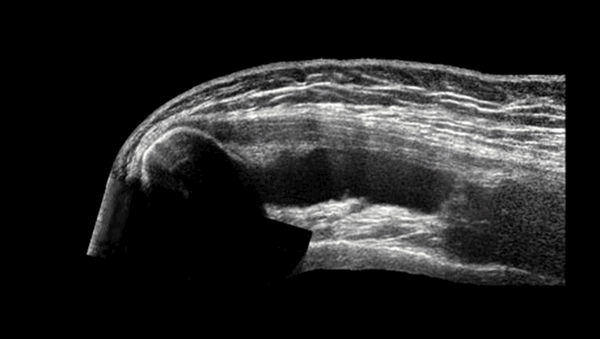

Что лучше УЗИ, КТ или МРТ плечевого сустава?

Врач назначает процедуру исходя из особенностей клинического случая. УЗИ применяют с целью экспресс-диагностики. Изображения, полученные с помощью ультразвука, недостаточно четкие, чтобы поставить точный диагноз. Метод малоинформативен на ранних этапах развития дегенеративно-дистрофических заболеваний. УЗИ плечевого сустава целесообразно при необходимости быстро оценить последствия травмы или исключить осложнения, или в случае противопоказаний у пациента к другим методам диагностики.

УЗИ плеча

УЗИ или МРТ плечевого сустава - что лучше

УЗИ и МРТ плечевого сустава - это два аппаратных метода диагностики структур плеча, а что из них лучше и в чем разница, давайте разбираться.

УЗИ или МРТ плечевого сустава - что лучше выбрать?

- Во-первых, ультразвуковое сканирование дает возможность оценить состояние сосудистой системы.

- Во-вторых, диагностику плеча пациента на УЗИ можно провести в движении, что в принципе недоступно для МРТ сустава, так как она требует полной неподвижности пациента.

- В-третьих, ультразвук не имеет никаких противопоказаний, и, в отличие от МРТ плеча, его можно проводить людям с металлом и электронными имплантами в теле, а также клаустрофобам.